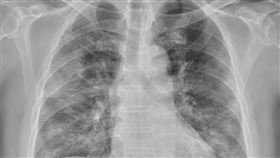

悚!40歲壯男突倒下 1病釀禍:無感卻奪命

抗疫千日 指揮中心解編

國人染新冠32%腦霧 靠中醫兩週「醒腦」

新冠疫情三年多來,不少民眾飽受長新冠所苦,一項針對長...

染疫病逝暴增4成!蘇一峰曝「急診慘況」

台灣新冠肺炎進入第四波疫情,近日出現反撲情況,上週確...